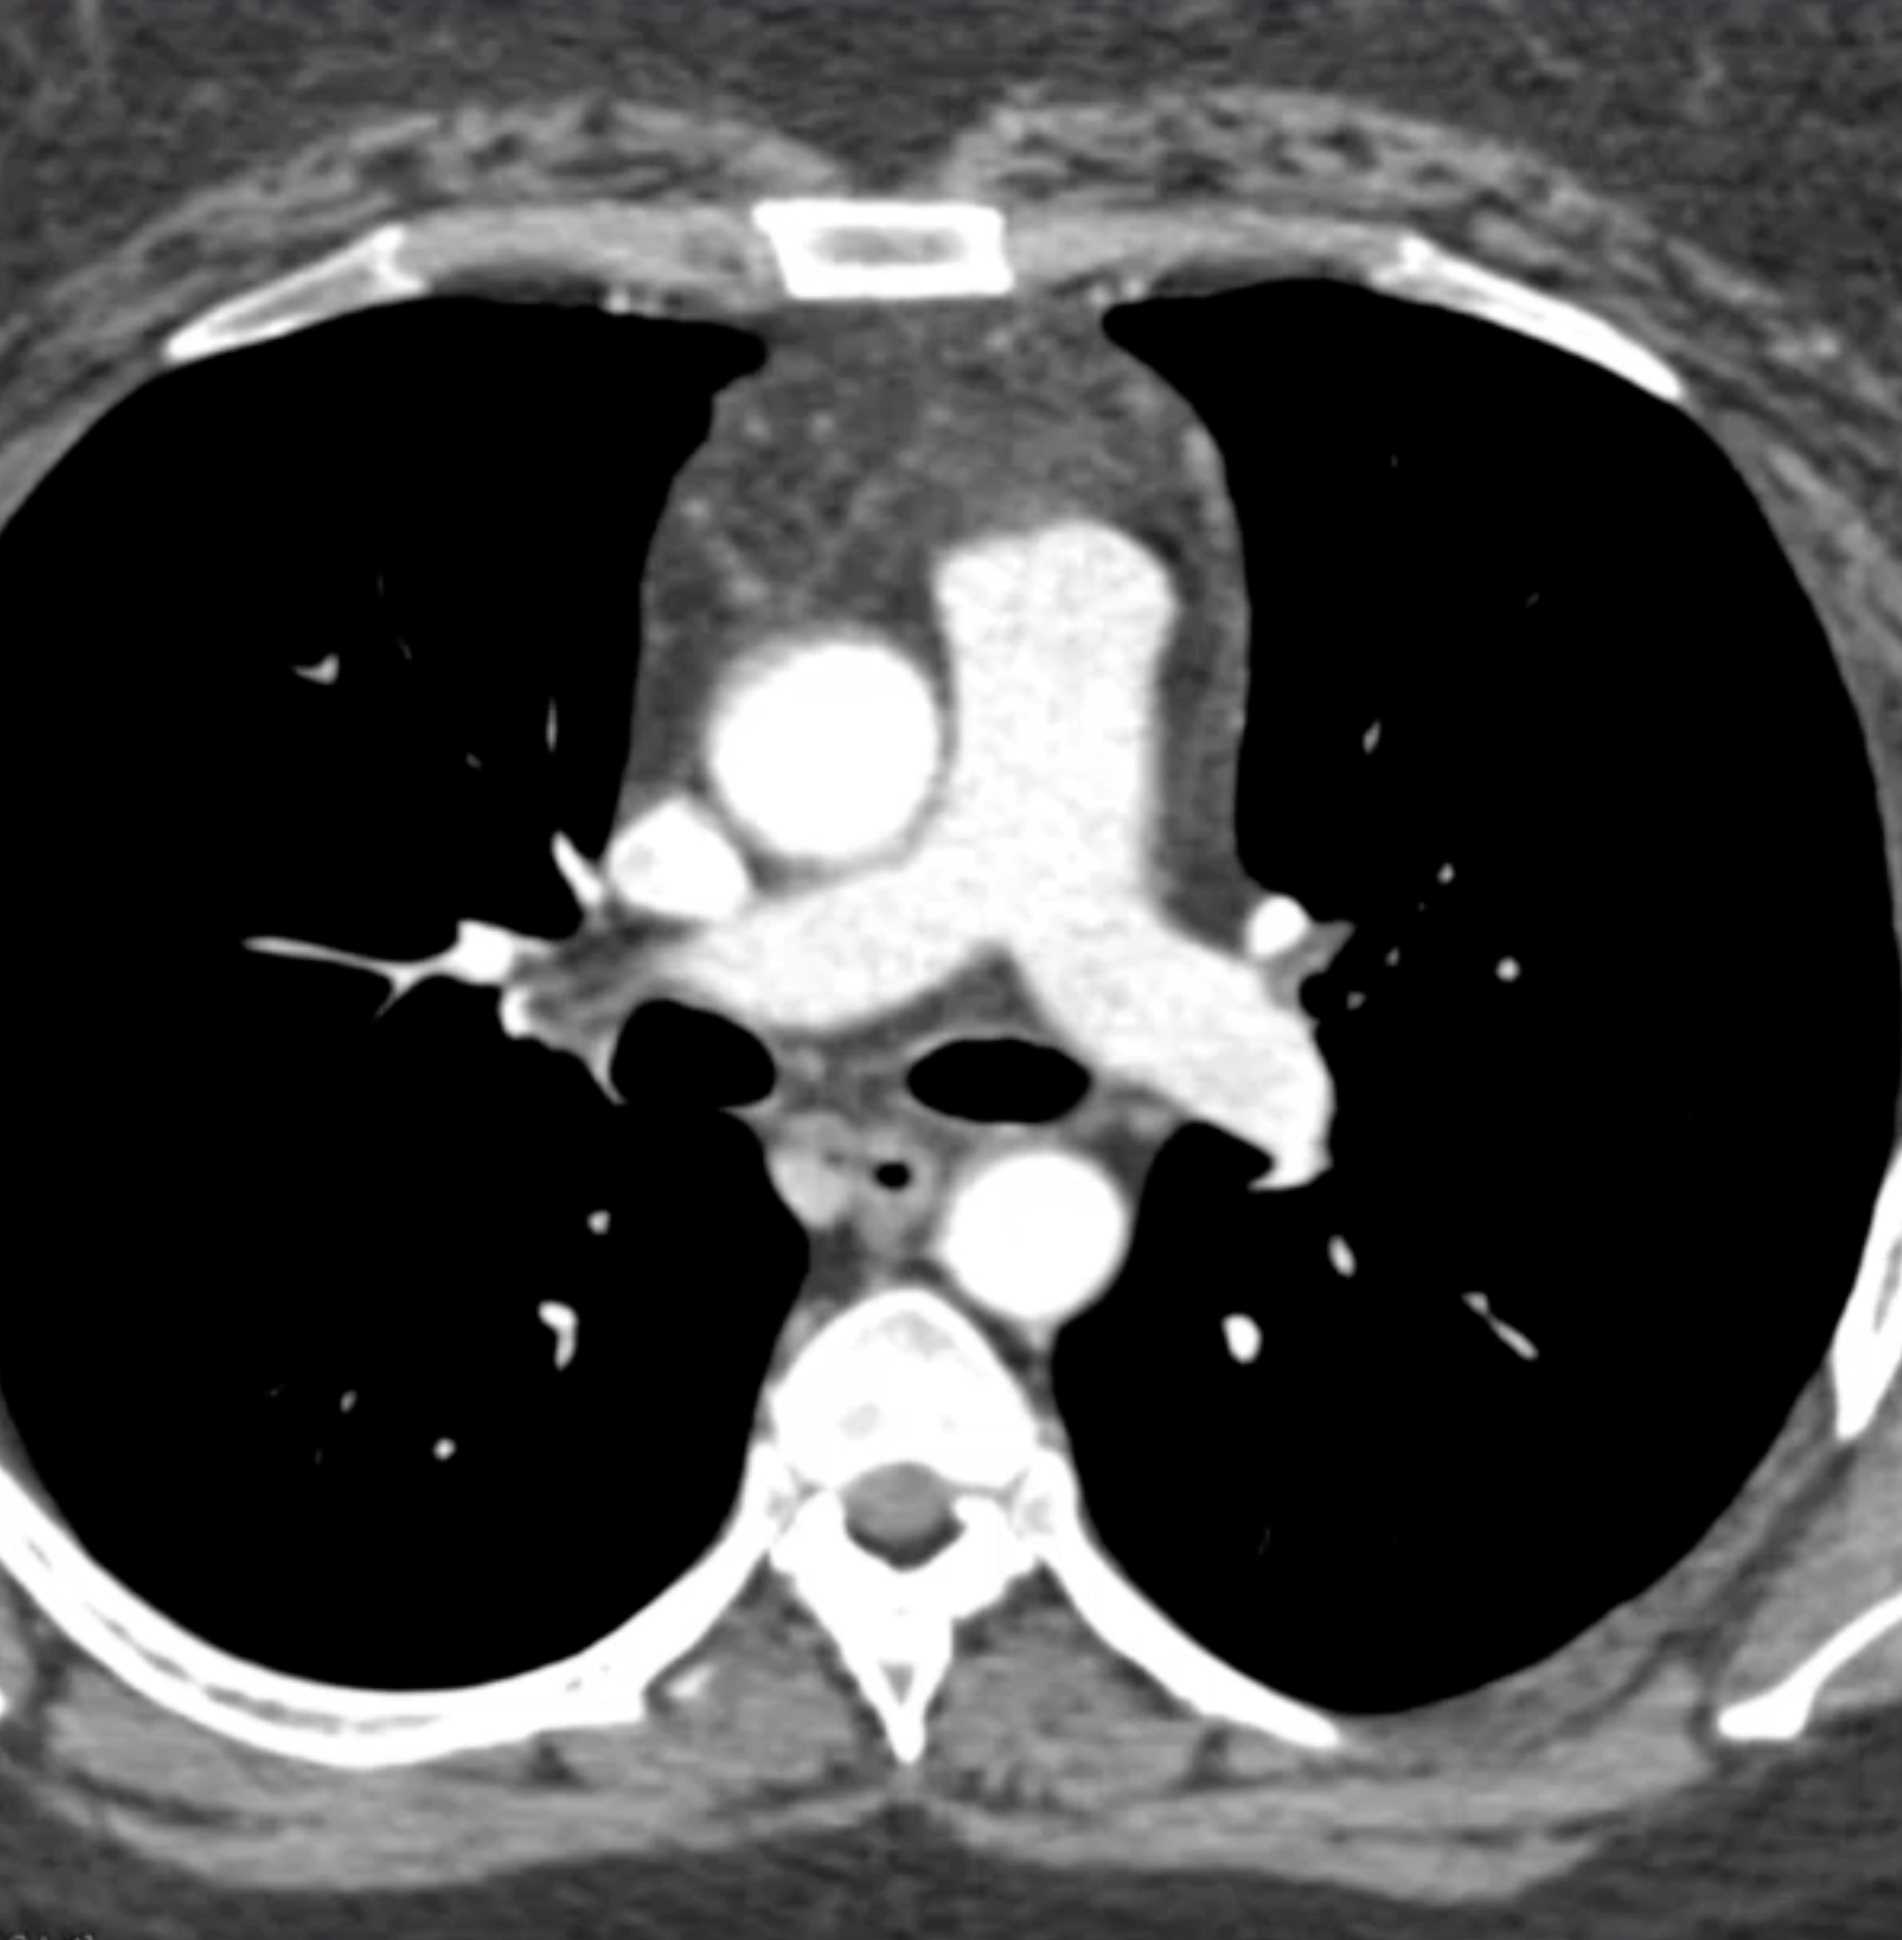

Thymolipoma